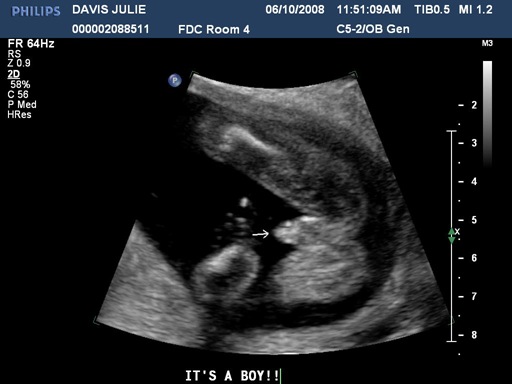

We went in for our first ultrasound today. It was a fun experience getting to see our first glimpses of the little life that is growing inside Julie’s belly. The ultrasound equipment at Winnie Palmer hospital is much better than when we had ultrasounds with our two daughters. But that was several years ago also. Seeing our baby’s little fingers, arms, heartbeat and all of the movements was a really neat experience. We also found out that we are having a little boy! We were all kinda hoping for that. Laurel and Marybeth were running around quoting a line from “Lady and the Tramp“…”Oh boy, it’s a boy! Oh boy, it’s a boy! Oh boy, it’s a boy!”

So…what does our baby look like now? Here are the five pics the hospital gave us (three are after the break). Also…if you don’t want to see the proof of “boyhood”, avoid the last picture.